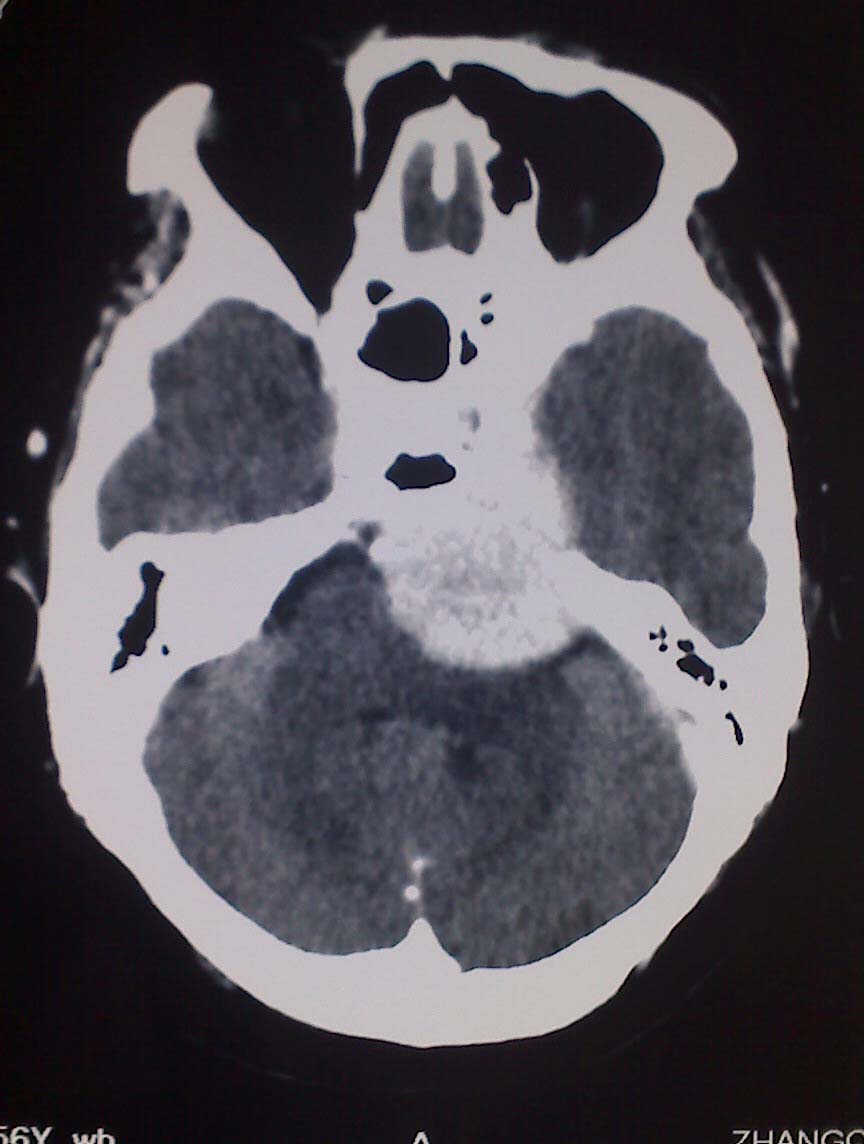

女性,56岁,查体所见,请会诊

平扫为较高密度,增强后病灶明显强化,边界清楚水肿不明显.考虑脑膜瘤.

左岩骨尖区脑膜瘤

从病变位置和强化表现看倾向脑膜瘤,但其跨越中后颅窝,也要结合临床,不能忽略三叉神经瘤,不过后者囊变较多。此病例的不足是无骨窗对照,脑膜瘤比较容易出现临近骨骼的异常。

左岩骨尖区占位病变,平扫呈高密度,病变跨中后颅窝生长,岩骨可见骨质吸收,周围未见明显水肿,增强扫描病灶明显强化。考虑左岩骨尖区脑膜瘤。

此片最大的缺憾是没骨窗,钙化及颅骨的改变不好看